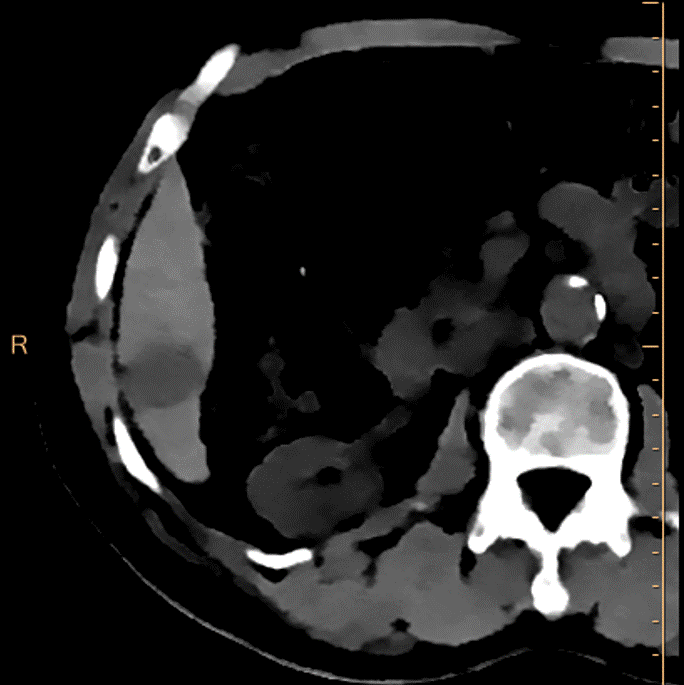

72 year old male, with chronic hepatitis C, genotype 6 (could not complete treatment), presents with weight loss. Past history of HCC with chemoebolization. AFP is normal. A CT scan with liver protocol is ordered. Turns out he also has chronic renal failure with eGFR in the 30’s. BMI is 21.

Patient is in the department for the scan. We decide to use Spectral CT to reduce dose of contrast. After a true non-contrast scan (done as he had previous chemoembo), the multiphasic scan is done with 35 mL of omnipaque 350.

On images below, it is obvious Spectral CT helps in many ways. On the non-contrast phase, the 2.4 cm lesion in segment 6 is so much more obvious on the electron-density image (you know I like EDW). On the arterial phase and delayed phase, the lesion shows enhancement and washout respectively, and both are so much better seen on the 40 keV monoenergy reconstruction. This is a liRADS 5 lesion(definite HCC).